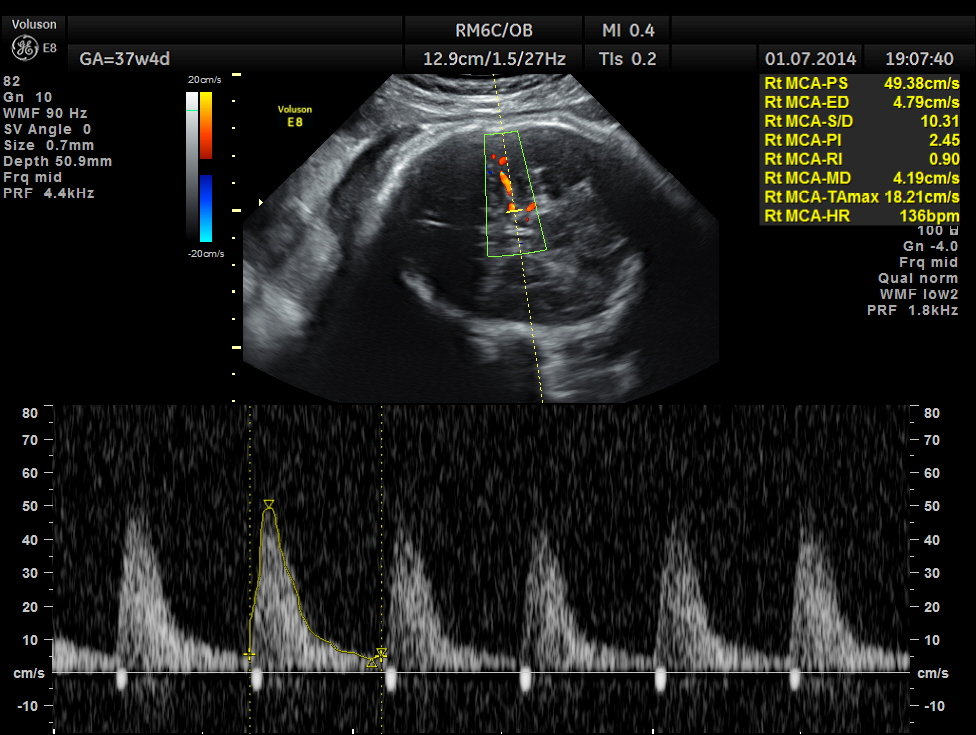

Spectral Doppler pictures are given below.

Umbilical arterial arterial P.I. and R.I. are high for the GA. and the cerebro placental ratio appears to be borderline > 1.0 and < 1.1 for the R.I.

The spectral Doppler pictures are given below

Umbilical artery R.I . AND P.I. appear to be normal now. The cerebro placental ratio is also normal.